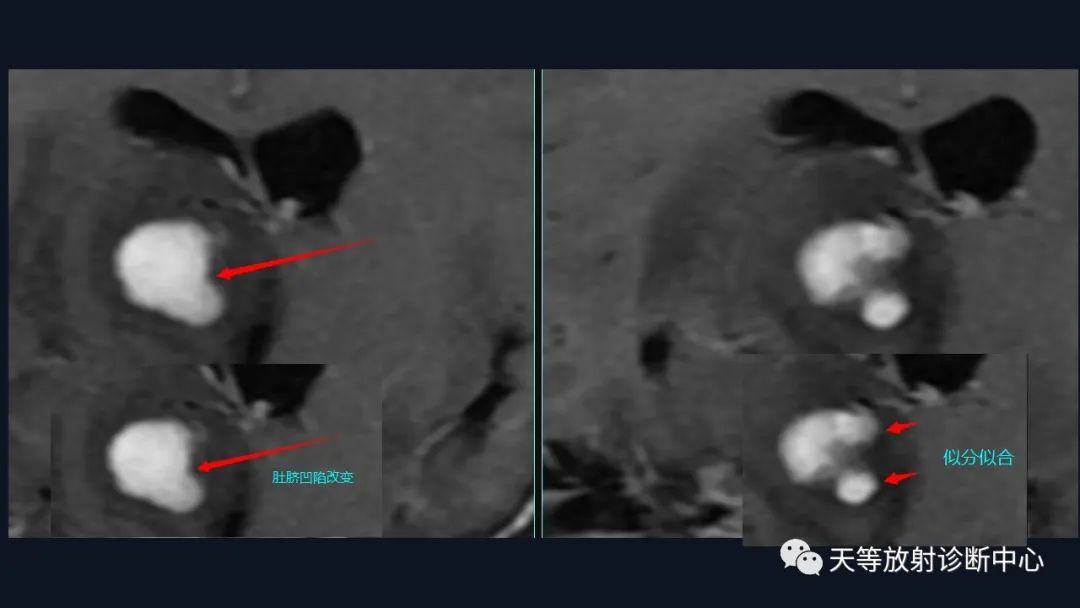

2、凹陷征或肚脐凹征

3、尖角征